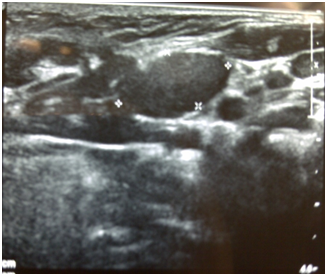

Figure 2 Ultrasound showing stone in the left parotid duct.

A variety of investigation modalities are available for diagnosis of parotid stones. Ultrasonography represents an excellent first‒level diagnostic technique because it reveals ductal and highly mineralized stones with a diameter of at least 1.5 mm with an accuracy of 99 %.7 Ultrasound can detect upto 90% of salivary duct stones. Stones appear as strongly hyperechoic lines or points with distal acoustic shadowing. Small stones (< 1.5 mm) may however not shadow.8 Ultrasound is able to visualise stones that are radiolucent. Some stones cannot be picked up on X‒ray films but can be easily seen on an ultrasound scan as 20‒40% of the stones are not radio‒opaque.9